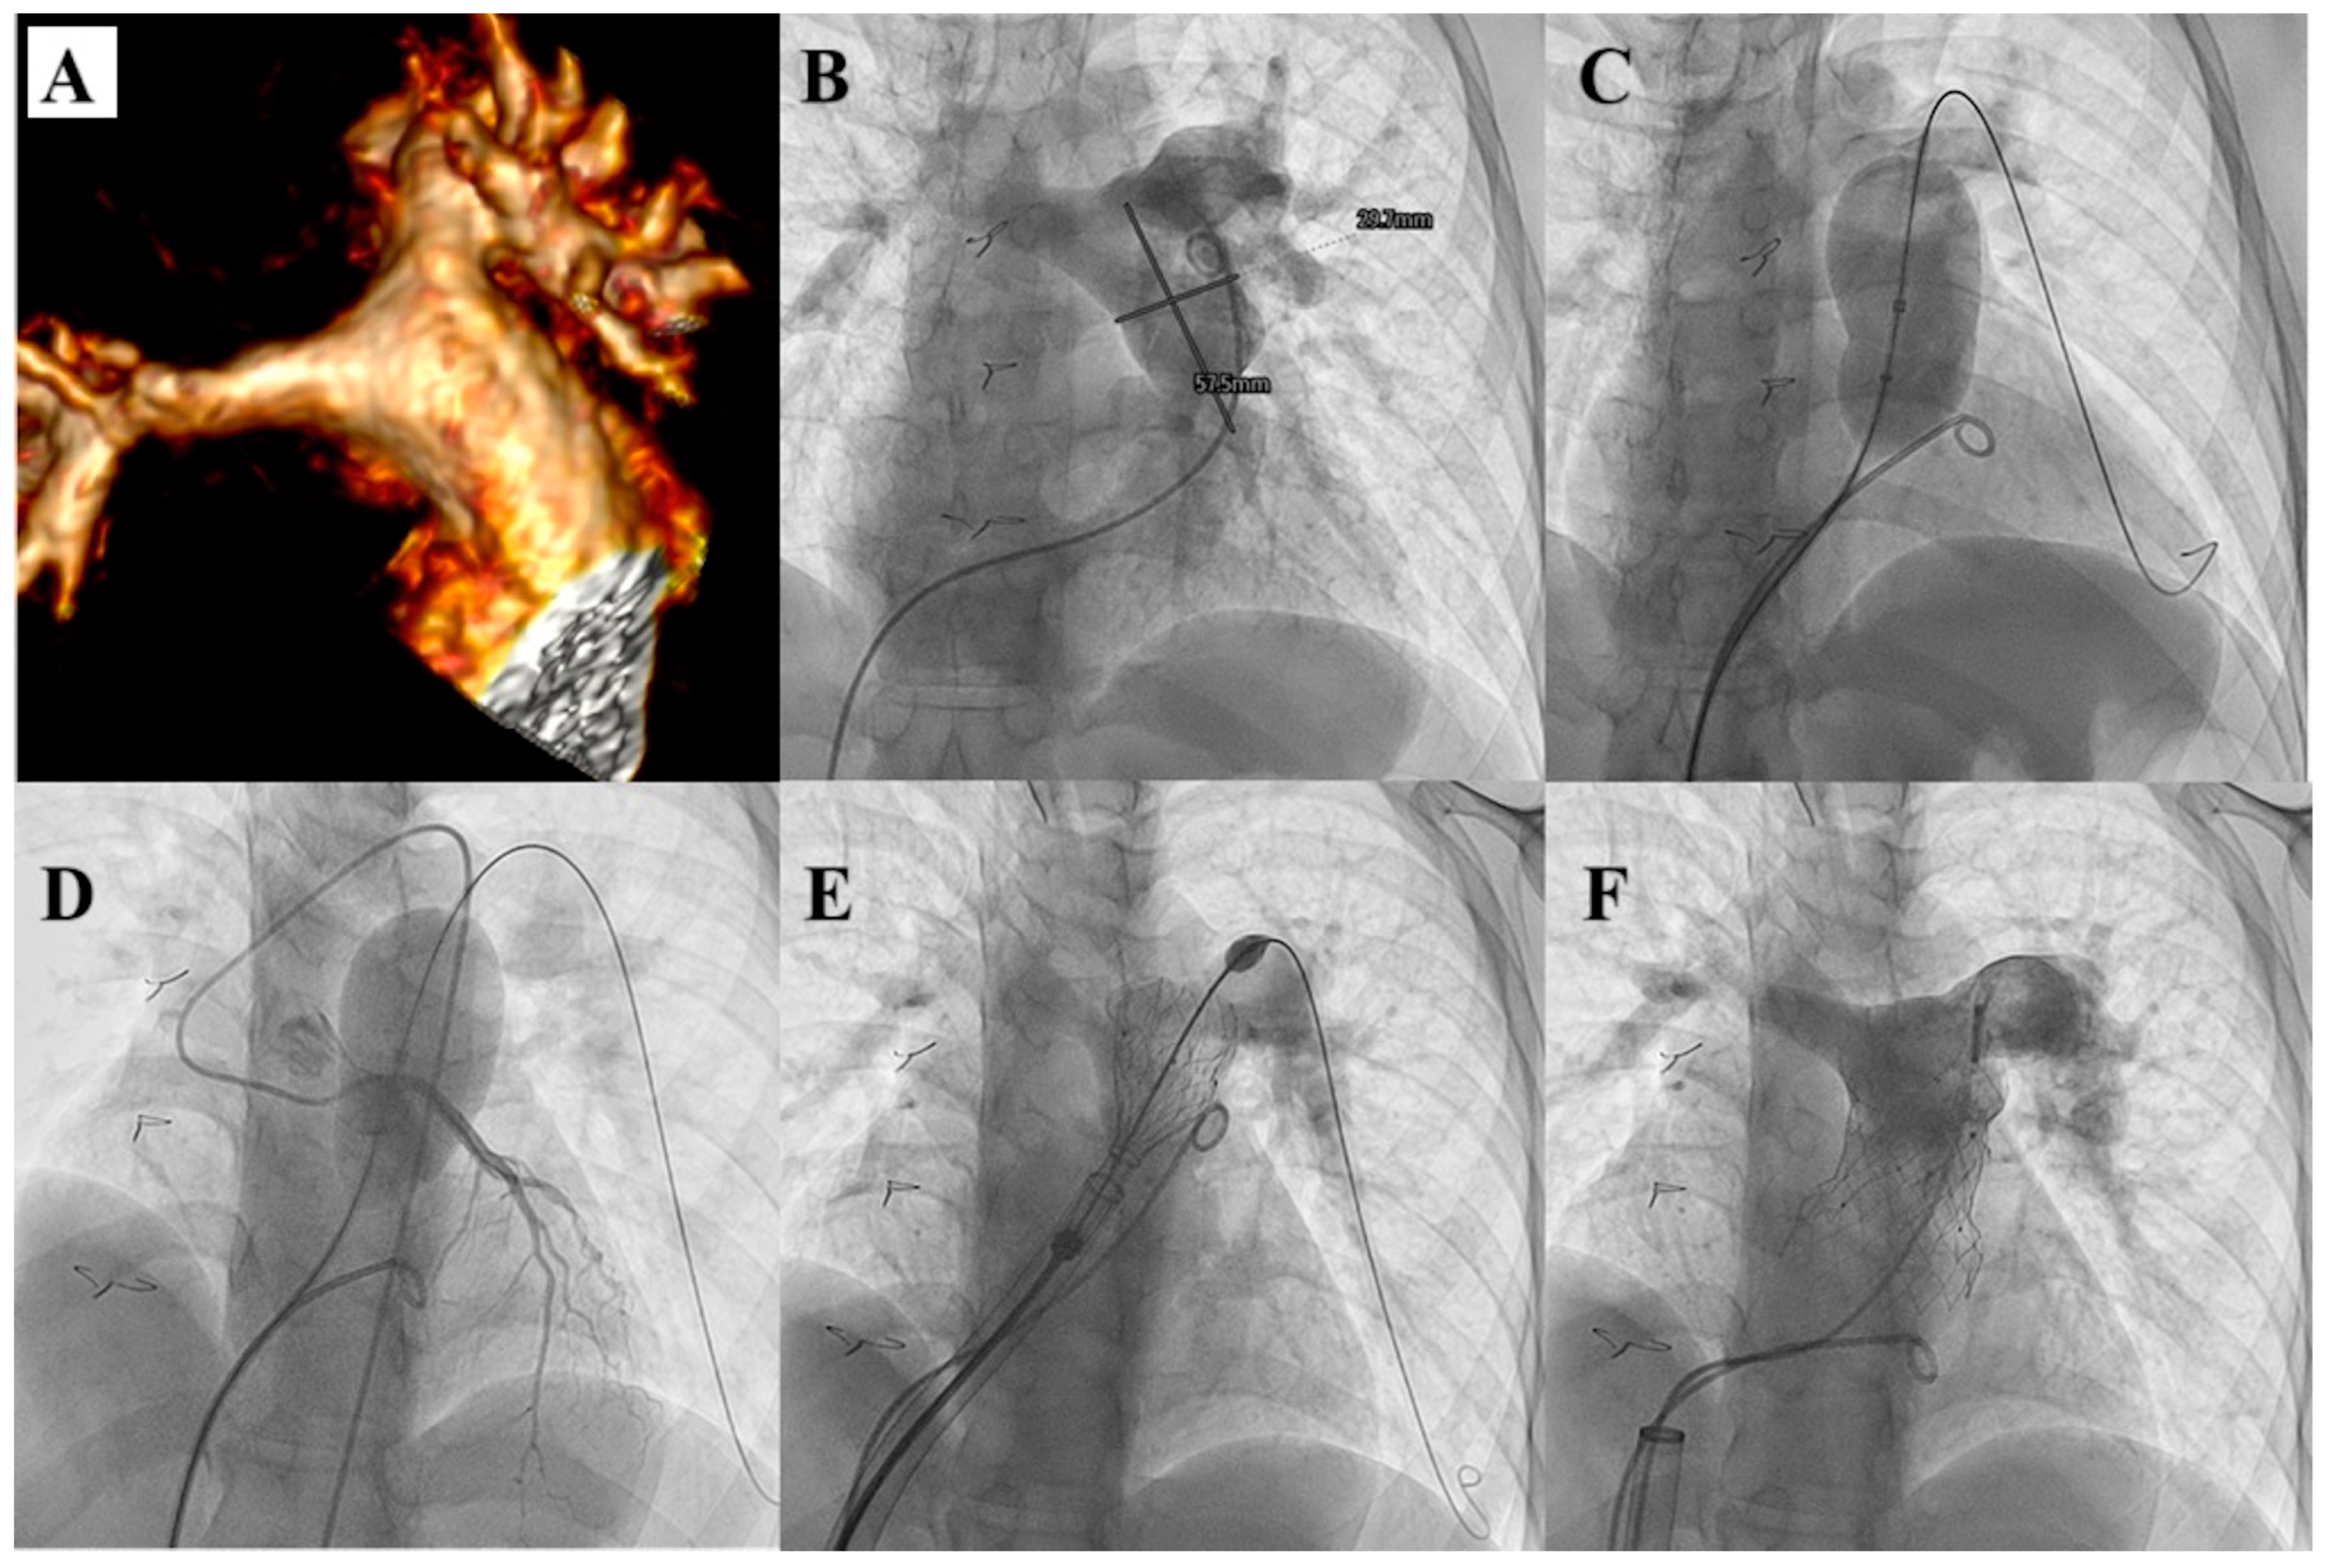

- Gillespie, M.J.; Benson, L.N.; Bergersen, L.; Bacha, E.A.; Cheatham, S.L.; Crean, A.M.; Eicken, A.; Ewert, P.; Geva, T.; Hellenbrand, W.E.; et al. Patient Selection Process for the Harmony Transcatheter Pulmonary Valve Early Feasibility Study. Am. J. Cardiol. 2017, 120, 1387–1392. [Google Scholar] [CrossRef] [PubMed]

- Gillespie, M.J.; Bergersen, L.; Benson, L.N.; Weng, S.; Cheatham, J.P. 5-year outcomes from the harmony native outflow tract early feasibility study. JACC Cardiovasc. Interv. 2021, 14, 816–817. [Google Scholar] [CrossRef]

- Gillespie, M.; McElhinney, D.; Jones, T.; Levi, D.; Weng, S.; Cheatham, J. Midterm outcomes from the harmony transcatheter pulmonary valve pivotal trial and continued access study. Pediatr. Cardiol. 2021, 42, 1903–1904. [Google Scholar]

- Levi, D.S.; Gillespie, M.J.; McElhinney, D.B.; Jones, T.K.; Benson, L.N.; Justino, H.; Haugan, D.; Cheatham, J.P. One-year outcomes in an expanded cohort of harmony transcatheter pulmonary valve recipients. J. Soc. Cardiovasc. Angiogr. Interv. 2022, 1, 100326–100327. [Google Scholar] [CrossRef]